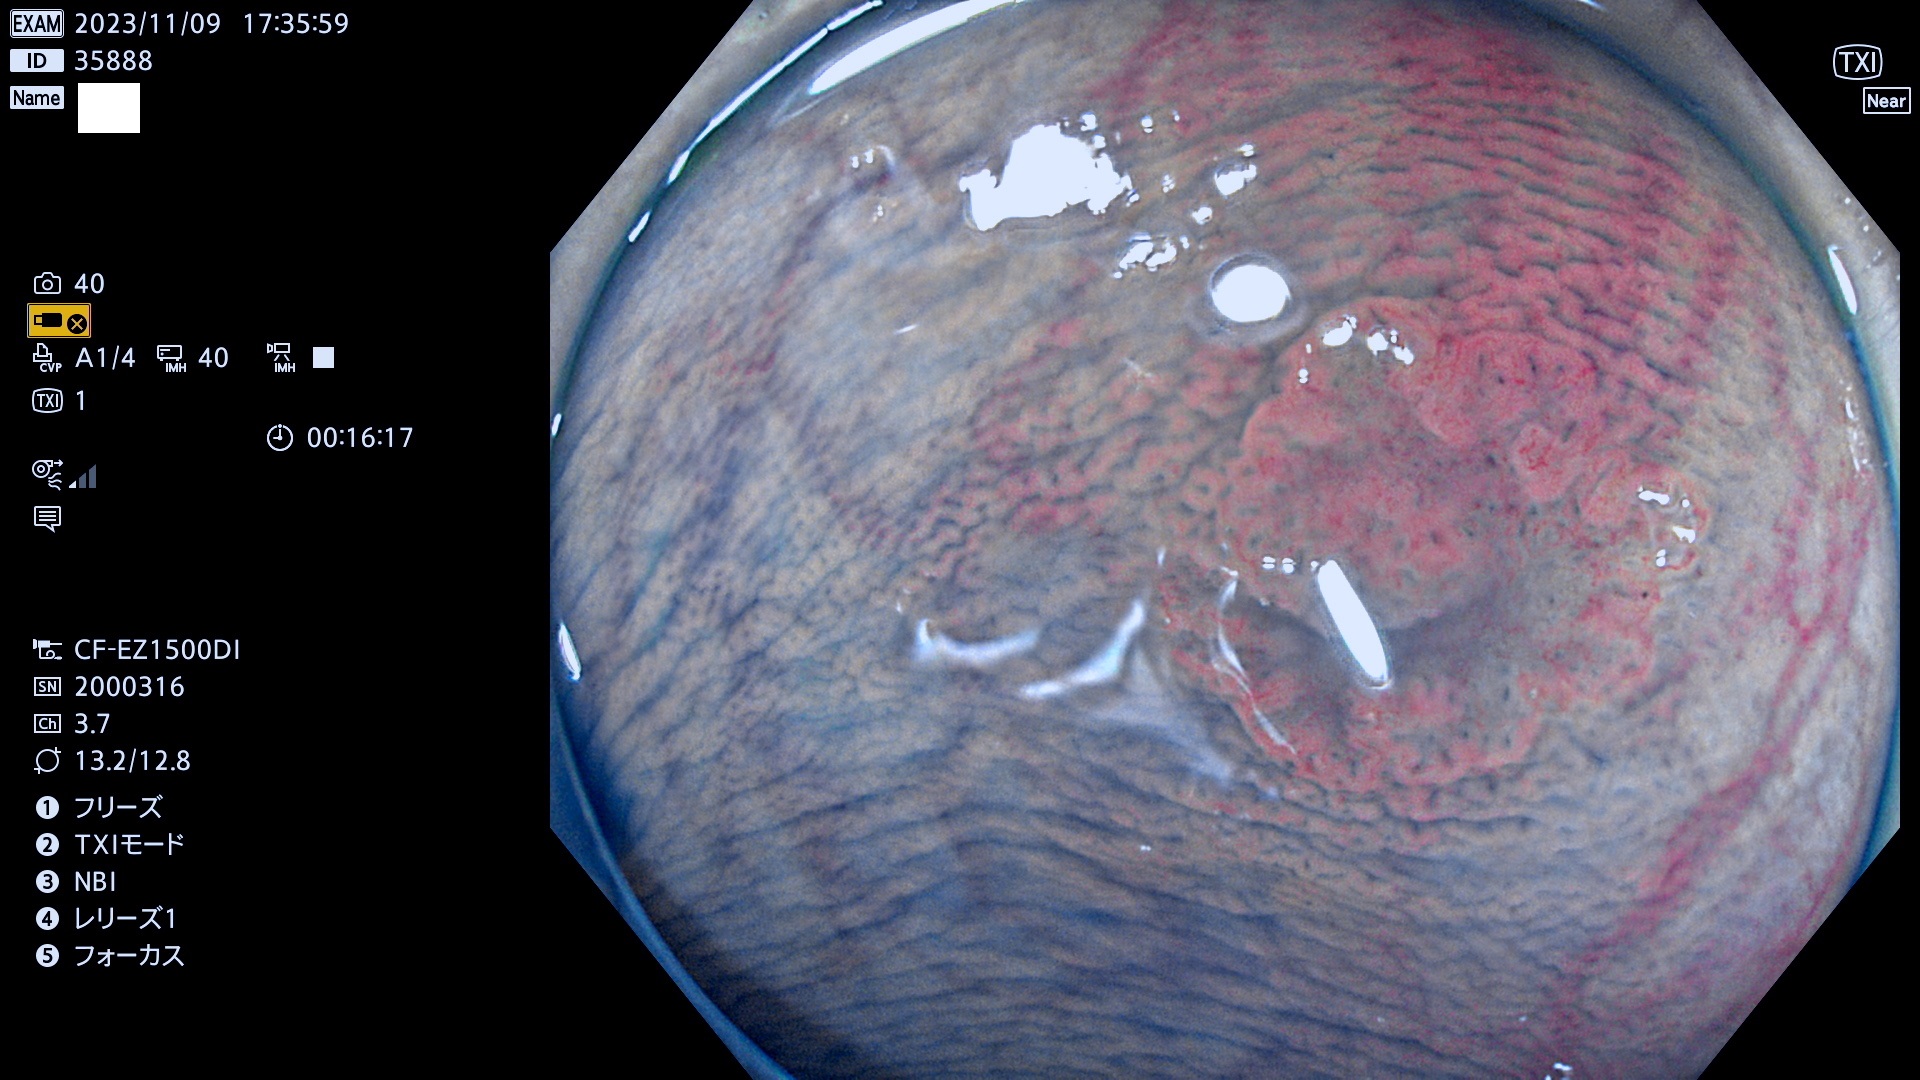

表面型腺腫(Flat Adenoma)の中で、完全に平坦な物をUb、陥凹している物をUcと呼びます。平坦隆起型(Ua)よりも、発見が難しく危険な病変です。このタイプは「内視鏡後・大腸癌の重要犯人」であり、この発見率は「腺腫発見率」よりも、重要な意味があります。

毎週の検査(木・金・土・日)に発見されたUb、Uc型・腺腫を、その週の日曜の夜にUPし1週間、提示します。

抽出の対象期間 2023年11月9日(木)〜11月12(日)の4日間(48件の検査)5件